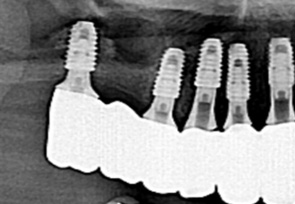

미국치과 임플란트 학회(AAID)의 인정의(AF. Associate.Fellow)인 일등플란트치과의 한순일 대표원장이 다 년간의 많은 임상경험 노하우를 바탕으로 구강 상태에 따른 적합한 뼈이식을 통해 임플란트에 적합한 뼈의 두께를 확보한 후 식립을 합니다.

잇몸뼈에 심은 임플란트가 잇몸뼈에서 단단히 고정되면 인공치아 보철물을 올려 치아부분을 완성합니다. 일등플란트 치과는 병원 내에 별도의 기공소가 있어 나의 자연 치아와 가까운 자연스러운 보철물을 빠르고 꼼꼼하게 제작합니다.